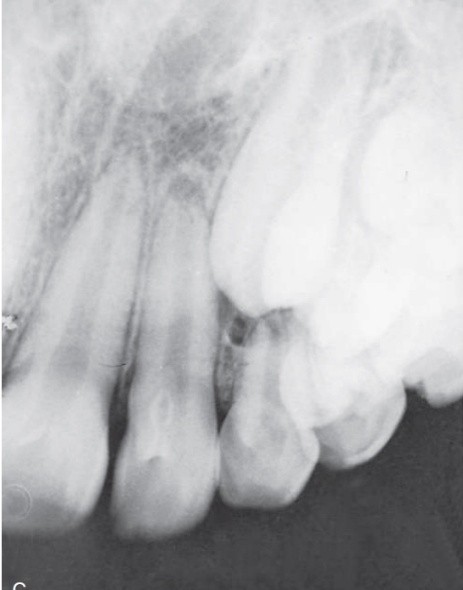

1. (Select ONE OR MORE correct answers)

The radiograph shows evidence of